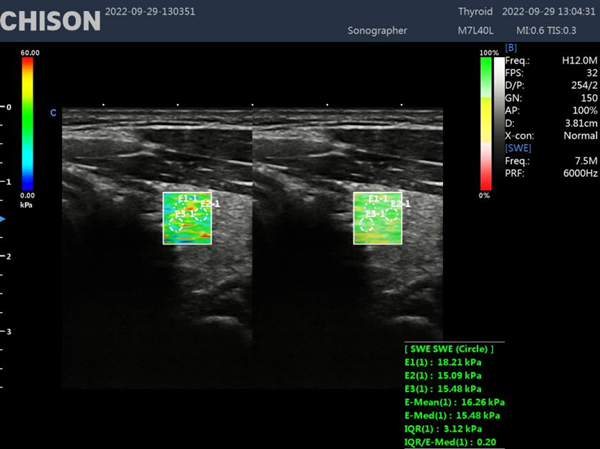

Shear wave elastography is a non-invasive imaging technique that measures tissue stiffness by generating and analyzing shear waves within the body. By utilizing ultrasound technology, shear wave elastography offers a unique perspective into the mechanical properties of tissues, enabling healthcare professionals to diagnose a wide range of conditions accurately.

Shear wave elastography relies on the propagation of shear waves through tissues. These waves are generated by the application of acoustic radiation force, which causes displacements within the tissue. By measuring the speed at which these waves travel, shear wave elastography can determine the elasticity and stiffness of tissues. This information is then visualized using color maps, providing clinicians with valuable diagnostic information.

Thyroid Nodule Assessment

Shear wave elastography has also found application in the evaluation of thyroid nodules. Determining the stiffness of these nodules, it assists in distinguishing between benign and malignant lesions, reducing the need for unnecessary invasive procedures.

Shear wave elastography represents a significant advancement in the field of diagnostic imaging. With its ability to assess tissue stiffness non-invasively and provide valuable diagnostic information, this technique has revolutionized medical imaging across various specialties. From liver disease assessment to breast lesion characterization and musculoskeletal evaluations, shear wave elastography continues to enhance our understanding and management of numerous conditions. XBit 90 has both P-SWE point shear wave imaging and 2D-SWE surface shear wave imaging. Provide a variety of quantitative analysis parameters, such as velocity values, Young's modulus, and so on. Embracing this cutting-edge technology can empower healthcare professionals to deliver superior patient care and make more informed clinical decisions.